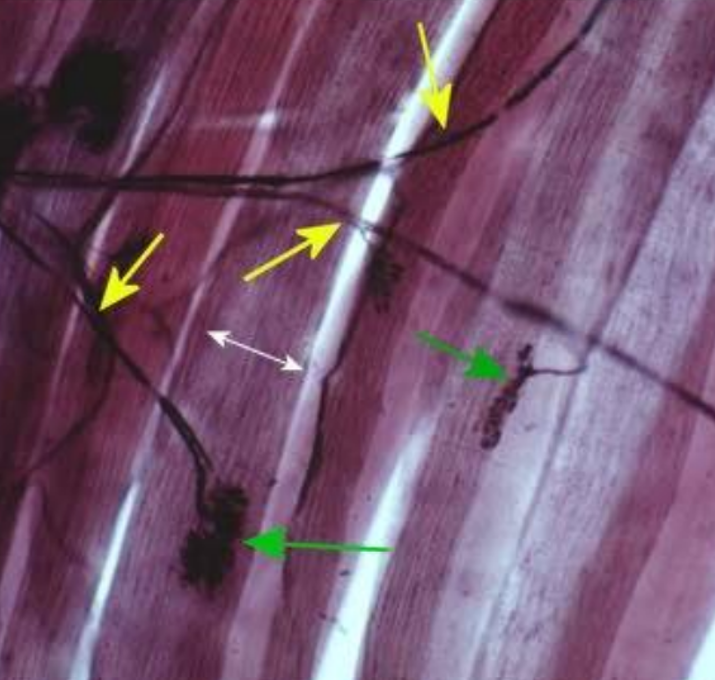

What cross section is this?

Skeletal muscle

What is the BLUE arrows pointing to?

epimysium

What is the YELLOW arrows pointing to?

endomysium

What is the GREEN arrows pointing to?

perimysium

What is the pointer on?